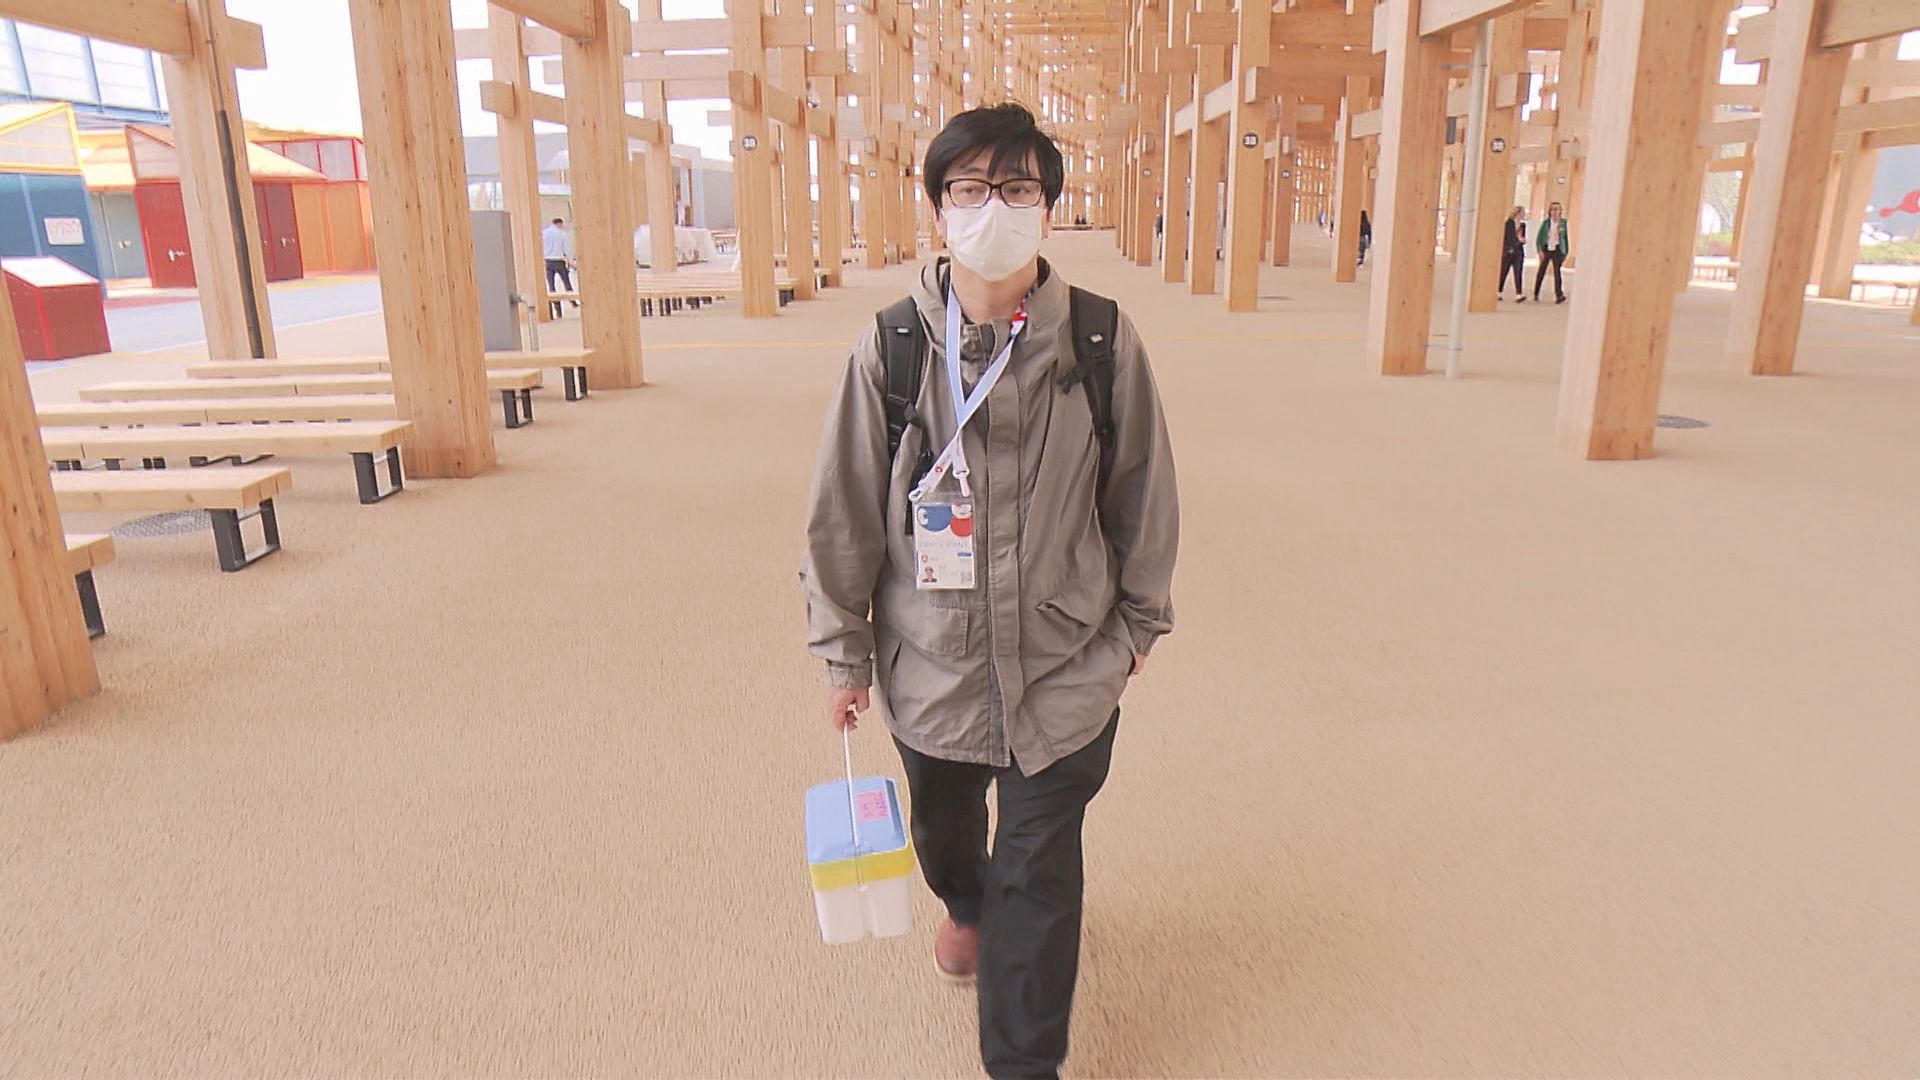

■「立体的な心臓を見せよう」提案した科学者

そこで、「立体的な心臓の形をやりましょう」と提案した科学者がいる。

研究部の長谷川光一部長だ。

【クオリプス・長谷川光一博士】「心筋シートだと『それで心臓なんだよ』と言われても『あっそう』という感じなんです。それが心臓の形をしているとなると、『心臓の細胞で生きているんだ』ということを皆さんに伝えることができるんじゃないかと思ったんです」

■生き物大好き少年「なんでこんな形をしているの」 生物科学者の道へ

有明海を望む熊本県玉名市で生まれ、大自然に囲まれて育った長谷川さん。

生き物が大好きな少年だった。

「ちっちゃいころは命を救おうなんて、全然何も考えてないです。親は阿蘇の農業高校の先生もしていたので、いっぱい色んな生き物に触れることがありましたね。図鑑で見たことのない生き物や、テレビで見たことのない生き物を見ると『なんでこんな色んな形があって、いろんな生き方があるんだろう』と興味を持ちました」

「すごい怒られましたね、ヘビを捕まえると。危険だから触るなと(笑)。隣近所のおっちゃんたちに怒られましたよ。毒を持っているか、頭の形で見分けろと言われました」

■「医者の手から『こぼれ落ちる命』を救いたい」

生物科学者への道を進んだ長谷川さん。

京都大学再生医科学研究所に在籍していた時に、その後の人生を変える出来事があった。

【クオリプス・長谷川光一博士】「喫煙所が肺結核病棟の近くにあったんですけど、患者さんもタバコを吸いにくるんです。そこで『最近暑くなりましたね』『寒くなりましたね』っていう何気ない話をしていた患者さんが、突然来なくなって。その時はやっぱりショックでしたね。つい先日まで『こんにちは』って言っていた人が亡くなりましたって聞くと」

医師ではないが、科学者の立場で人の命を救いたい。

長谷川さんの中で、そんな思いが芽生えたという。

【クオリプス・長谷川光一博士】「自分の持っている技術で人を救えるようになりたいと思いました。お医者さんって特別なんですよ。それだけ努力してきているし、責任も重い仕事をしておられると思うんですけど、お医者さんたちと博士との間では、クリアなボーダーがあるんです。お医者さんの世界と、研究者の世界と、そこをつないだり、乗り越えらたりできるようになりたいという気持ちがありました」

「この技術でたくさんの人を救えればいいなって。お医者さんと科学者が違うのは『お医者さんの手からこぼれ落ちる人がなくなるようにしましょう』っていうこと。もっと土台なんですよね僕ら科学者がやっていることって」

2022年、長谷川さんは澤教授に誘われ「クオリプス」の一員となり、現在に至る。

万博開幕の2年前、iPS細胞由来の心筋細胞を使った「立体的な心臓の形」をつくるという、長谷川さんの提案をベースにプロジェクトは始まったが、そう上手くはいかなかった。

万博に展示するiPS心臓モデル開発でも奥田さんのひらめきが数々のピンチを救った。

■「ぶら下げた方がいいんです」強く拍動した心臓

そこで奥田さんが提案したのが、実際の心臓と同じく、縦にして吊り下げるという手法だった。

iPS心臓モデルにナイロンの細いワイヤ―を通し、培養液の中で吊り下げると、実際の心臓と同じように拍動したのだ。

【クオリプス・長谷川光一博士】「寝かしたままで、鏡を置いて立っているように見せることができればいいという意見もあったんですけど、奥田さんの『いやいや吊ってみましょうよ』っていうアイデアで吊り下げてみたら、平面でいるときよりも、心なしか拍動が自然の形に近いのか、強い感じがしてですね、不思議だなと思って」

「万博が終わったら、何が起こっているのか研究しようと思っているんです。吊り下げると拍動が強くなるので、何かしらのことが起こっていると思うんです」

奥田さんの「心臓を吊り下げる」という発想には、研究を見守っていた澤教授も驚いたという。

【大阪大学・澤芳樹特任教授】「もう突然、開幕の1年ぐらい前に、奥田君が僕に『心臓が動き出しました』って言ってくれたんです。それまでは、ほとんど動いてなかったんですよ。こんなこと技術的にできるわけがないと思っていたら、奥田君が『できた』っていうから、『ほんまか?』って言って。それで、奥田君が『ぶら下げた方がいいです』と」

「糸で吊ることで、動き出すということがわかったので、これも『サイエンス』ですよね。吊らなかったら動かないのに、吊ったら必ず動くんだというところで再現性がある」

「なぜ吊ったら動くかということが大事で、おそらく心筋細胞に与える重力とか、いろんな影響があるのかもしれない。もともと持っている遺伝子じゃなくて、環境因子がそういう影響を与えて、細胞の性格を変えたがために、寝ていたら動かなかったのが、立てたら動くようになるというね」

【クオリプス・長谷川光一博士】「iPS心臓モデルは、まだ小さいですし、けれども健気に自律で拍動するんです。『不思議だな、これを研究して治療までもっていきたい』と思うような人たちが出てくればいいなと思っています」

Q.出てこられると思いますか?

「いやぁ、出てこられないと困りますね。絶対、出てくると思いますよ。僕らだって、ちっちゃい時に、色んな生き物を見て『これは、どうしてこんなことになっているのか知りたいし、解明したい』と思ったので」

「この心臓を見た何人かの子どもたちは、『まだこんなところか。ならまだこれからだな』と思って、『これから自分がiPS心臓を治療に用いるんだ』って思う人が出てきてくれると信じています」